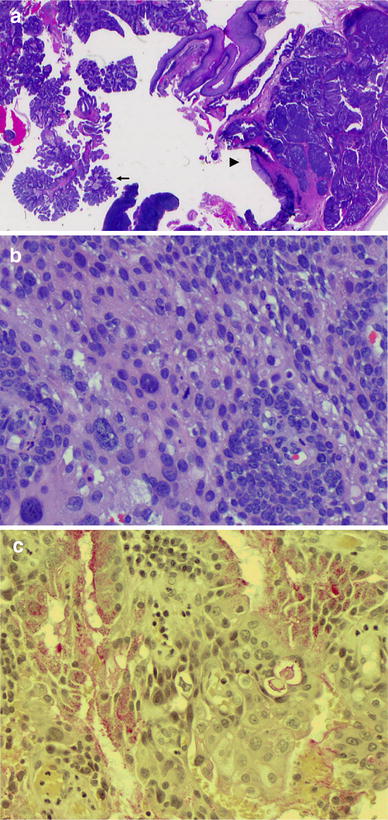

The deeper and malignant portion of the tumor grows in a more solid pattern with well defined squamous differentiation (Figs. 1c, 2a, b), intermediate cells, and nests of gland-like structures. Scattered foci demonstrate definitive mucin-positive tumor cells (confirmed by mucicarmine stain, Sigma-Aldrich, St. Louis, MO) (Fig. 2c), which are focally intermixed with the squamous component. Nuclear pleomorphism, hyperchromasia, and high mitotic activity are evident in the squamous component, which is in close association with adjacent salivary ductal epithelium, and with the deeper portion of sialadenoma papilliferum (Fig. 2a). In many areas, the malignant tumor obliterates the benign lesion and infiltrates beyond the confines of the sialadenoma papilliferum. However, the sialadenoma papilliferum component retains its papillary and proliferative configuration, mostly at the surface (Fig. 2a). Our diagnosis was therefore high grade (Brandwein grading system) mucoepidermoid carcinoma arising in a background of sialadenoma papilliferum [7]. The followup re-excision and nodal dissection specimens showed only squamous metaplasia of minor salivary glands, and mucosal ulceration.

Fig. 2

a Mucoepidermoid carcinoma arising in a background of sialadenoma papilliferum. Arrow, superficial component of sialadenoma papilliferum. Arrowhead, deep portion of the lesion with mucoepidermoid carcinoma intermixed with sialadenoma papilliferum. 10×, hemotoxylin-eosin stain. b Mucoepidermoid carcinoma. Predominantly squamous component with high grade nuclear features. 400×; hemotoxylin-eosin stain. c Mucicarmine stain for mucoepidermoid carcinoma, demonstrating both intraglandular and intracellular mucin. 400×; Mucicarmine stain (Sigma-Aldrich, St. Louis, MO)